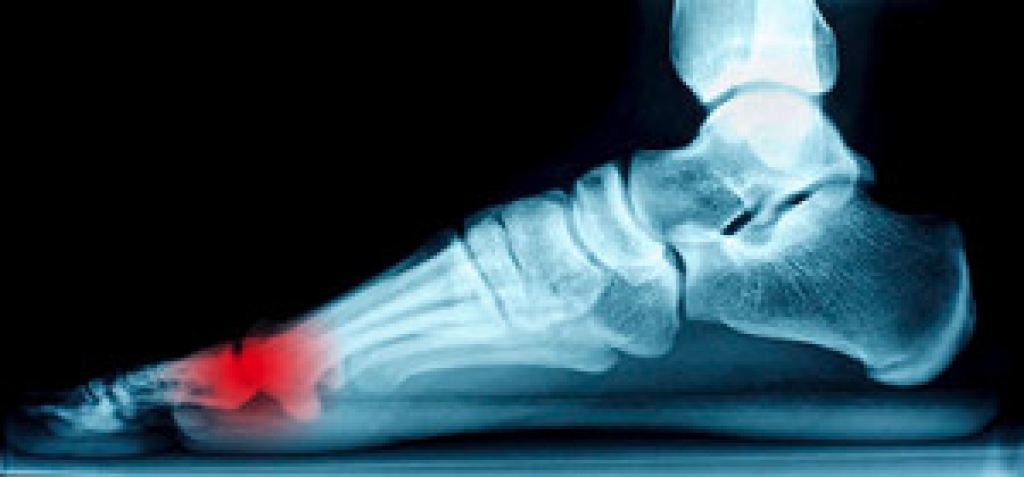

The bones in the body that are connected to the muscles by tendons are referred to as sesamoids. If the tendons in the feet become inflamed, a condition called sesamoiditis may develop. The symptoms that typically accompany this ailment may be swelling as a result of painful inflammation, which commonly occurs on the sole of the foot. The big toe is generally affected, and there may be difficulty in moving it. Women who frequently wear high heels may be at greater risk to develop sesamoiditis, in addition to athletes who participate in running sports such as basketball or soccer. A proper diagnosis is typically accomplished by having an X-ray of your foot performed, or in more severe cases, a bone scan, MRI, or ultrasound may be necessary. Research has shown that it’s helpful to cease the activity that may have caused this condition to develop, and this may alleviate painful symptoms. It’s advised to consult with a podiatrist for additional information on how to treat sesamoiditis.

Sesamoiditis is a condition of the foot that affects the ball of the foot. It is more common in younger people than it is in older people. It can also occur with people who have begun a new exercise program, since their bodies are adjusting to the new physical regimen. Pain may also be caused by the inflammation of tendons surrounding the bones. It is important to seek treatment in its early stages because if you ignore the pain, this condition can lead to more serious problems such as severe irritation and bone fractures.